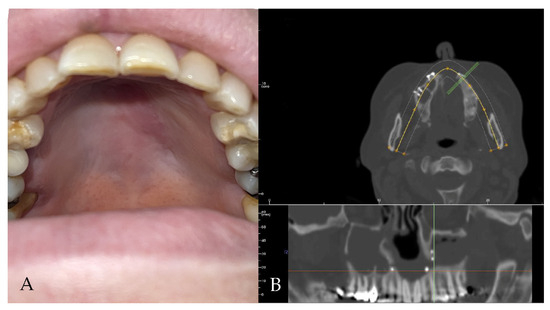

2.2. Case 2

A 52-year-old male patient came to our attention in 2017, presenting with a palatal/oro-nasal fistula measuring 3.5 cm in diameter along the major axis, with atrophic soft tissues surrounding the lesion (Ia according to the Okay et al. classification [14]). The patient had already been treated in 2015 in another center using a palatal local flap with no success and was then treated with an obturator. At the clinical and radiographic examination (Figure 4), a wide oro-nasal communication with exposure of the nasal cavity and septum was observed, leading to speech disturbances, rhinolalia, and eating difficulties.

Figure 4. (A) Clinical presentation of the oro-nasal communication. In inset A, it is possible to appreciate the visibility of the nasal septum. (B,C) Radiographic and 3D reconstruction using InVivo6® and Anatomage Table EDU vers.8® (Santa Clara, CA, USA) software. DICOM files were imported in InVivo6® (Santa Clara, CA, USA) software to obtain the axial, cross, and panorex sections. Afterwards, the DICOM files were imported into Anatomage Table EDU vers.8® (Santa Clara, CA, USA) to obtain the 3D rendering.

In 2018, after 4 years of sobriety, the patient underwent surgical intervention for palate reconstruction. The Le Fort I osteotomy was preceded by preplating to achieve the correct repositioning of the fragment (Figure 5). A careful dissection of the nasal and palatal mucosa was performed after the down fracture. A temporalis muscle rotation flap was harvested on the right side. The operation lasted three hours in the oro-tracheal tube. A nasogastric tube was placed and kept in place for seven days with standard antibiotic and anti-inflammatory therapy. The patient was discharged after four days.

Figure 5. The surgery was performed, using a Le Fort I osteotomy preceded by preplating to achieve the correct repositioning of the fragment; a careful dissection of the nasal and palatal mucosa was performed after the down fracture.